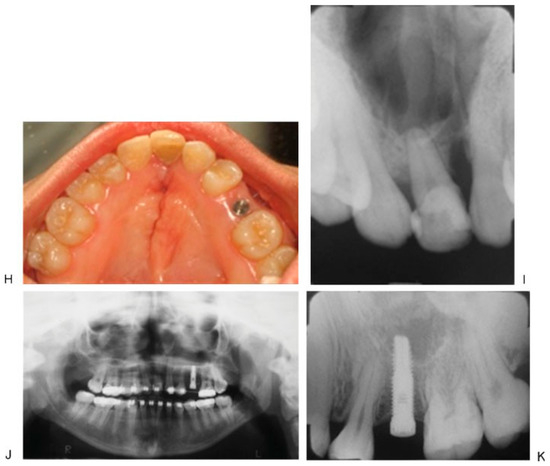

The Hyrax device is used in orthodontics to perform expansion through the palatal midsuture in growing patients. Its first use in maxillofacial surgery was to perform maxillary transverse distraction and later, expansion of the mandibular symphysis. At this time, there is no publication that proposes its use for alveolar bone transport, generally performed with specifically fabricated distracters, but its cost is a major disadvantage. Besides presenting major volume, there is difficulty with adjusting it and with big attachments for its activation. This impedes the management and thereby diminishes the tolerance on the part of the patients. The VEGAX device is a modification of the Hyrax, in which two of the dental bands are replaced with attachments that allow the placement of monocortical screws on the alveolar ridge: on the disk of transport and in the fixed segment. Both remaining bands anchor to the dental pieces: one in the fixed segment and the other one on the disk (Figure 1).

Figure 1.

(A–C) Modified Hyrax device (VEGAX) design. Hyrax screw modified with two upper loops for bone fixation (one for transport disk and the other in the nonmobile area) and dental bands welded (one in a tooth at the transport disk and the other in the firm dental arch).